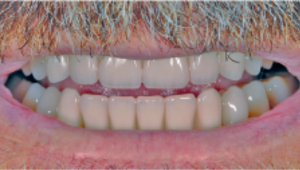

Resultado estético final tras la colocación de la prótesis definitiva, a un paciente con línea de sonrisa alta, sin compromiso visual de los accesos de tornillo. Caso clínico publicado originalmente en la revista científica Dentale Implantologie, Vol. 23, nº 2 (2019).